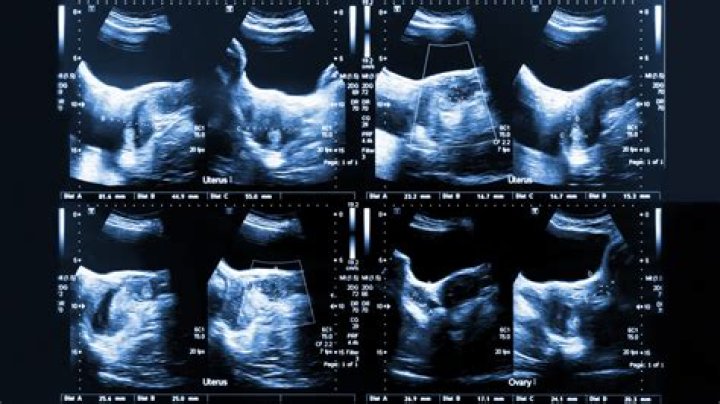

A pelvic ultrasound is a test that uses sound waves to make a picture of the inside of the lower belly (pelvis). It allows your doctor to see your bladder, cervix, uterus, fallopian tubes, and ovaries. The sound waves create a picture on a video monitor.

A pelvic ultrasound may be used to diagnose and assist in the treatment of the following conditions: Abnormalities in the anatomic structure of the uterus, including endometrial conditions. Fibroid tumors (benign growths), masses, cysts, and other types of tumors within the pelvis.

An abnormal result may be due to many conditions. Some problems that may be seen include: Abscess in the ovaries, fallopian tubes, or pelvis. Birth defects of the womb or vagina. Cancers of the bladder , cervix , uterus , ovaries , vagina , and other pelvic structures.